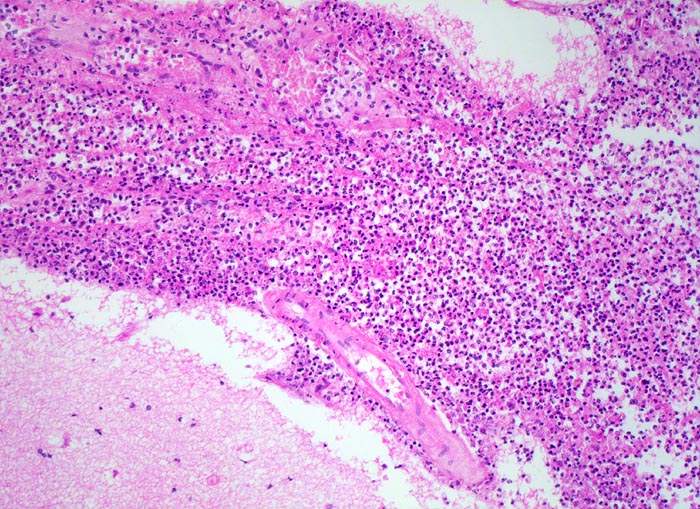

Der makroskopische Befund bei bakterieller Meningitis kann sehr diskret sein. Die meningealen Gefässe sind hyperämisch und die Hirnoberfläche wird von einem grüngelben Eiterbelag bedeckt (eher basal bei Hämophilus influenzae, eher über der Konvexität bei Pneumokokken=Haubenmeningitis). Histologisch ist der Subarachnoidalraum mit Eiter gefüllt. Bei weniger schweren Fällen finden sich die neutrophilen Granulozyten bevorzugt um die leptomeningealen Gefässe.

• Der verbreiterte Subarachnoidalraum ist mit Eiter und Ödemflüssigkeit ausgefüllt.

• Ein Teil der leptomeningealen Gefässe zeigt eine fibrinoide Nekrose der Gefässwand.

• Ein Teil der Gefässlumina angefüllt mit Fibrin und neutrophilen Granulozyten.